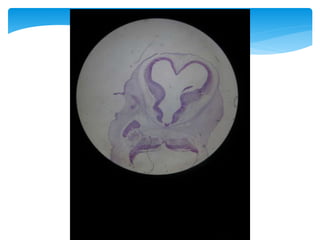

HEMISFERIOS CEREBRALES

 Se desarrollan a partir de la 5ta semana

 A la mitad del 2do mes  Crecimiento rápido de la porción

basal de los hemisferios

Sobresale hacia el interior del

Ventrículo lateral y

en el piso del agujero de Monro

Cuerpo

estriado